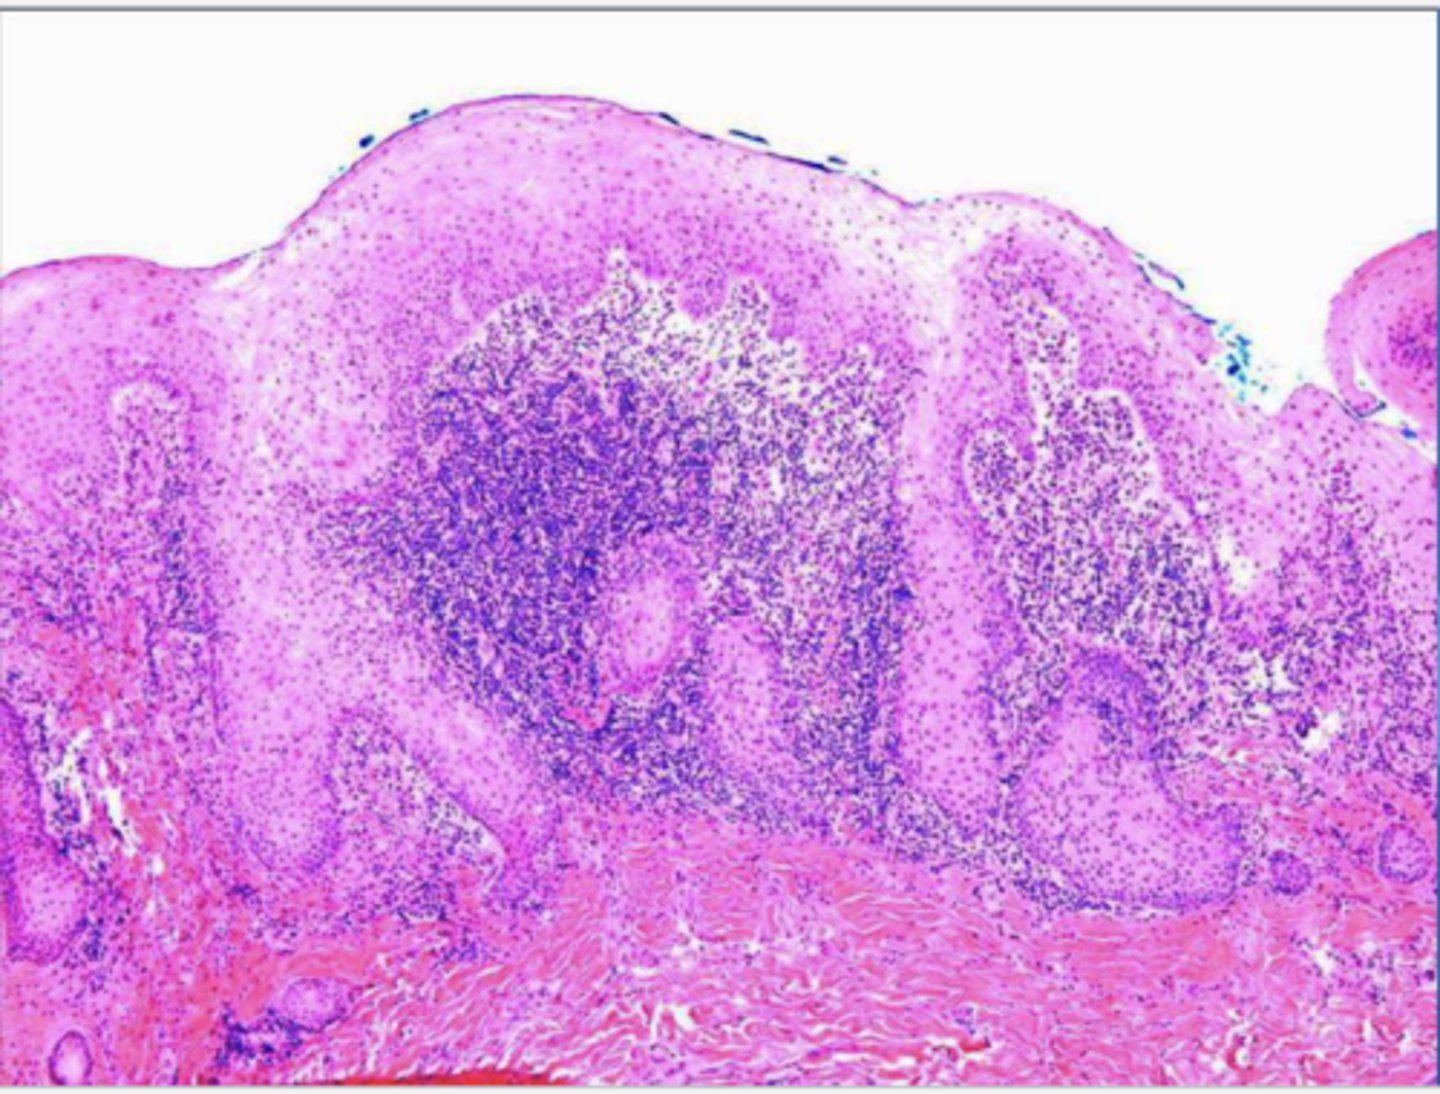

the following describe the histopathological features of what?

-hyperparakeratosis or hyperorthokeratosis

-papillary hyperplasia &/or pseudoepitheliomatous hyperplasia

-hyperplasia or connective tissue

epulis fissuratum

The following describes the histopathological features of what?

-papillary growths on surface

-may show pseudoepithliomatous hyperplasia

-sialadenitis

inflammatory papillary hyperplasia

why can an histological image of pseudoepithliomatous hyperplasia be mistakenly diagnosed as squamous cell carcinoma?

histo of epulis fissuratum has pseudoepitheliomatous hyperplasia that resemble cancer b/c rete pegs running thru the horizontal plane & we may be unable to see connection to surface due to the orientation of the section we're viewing --> so it looks like de novo formation of epithelia w/ CT = suspicion for cancer